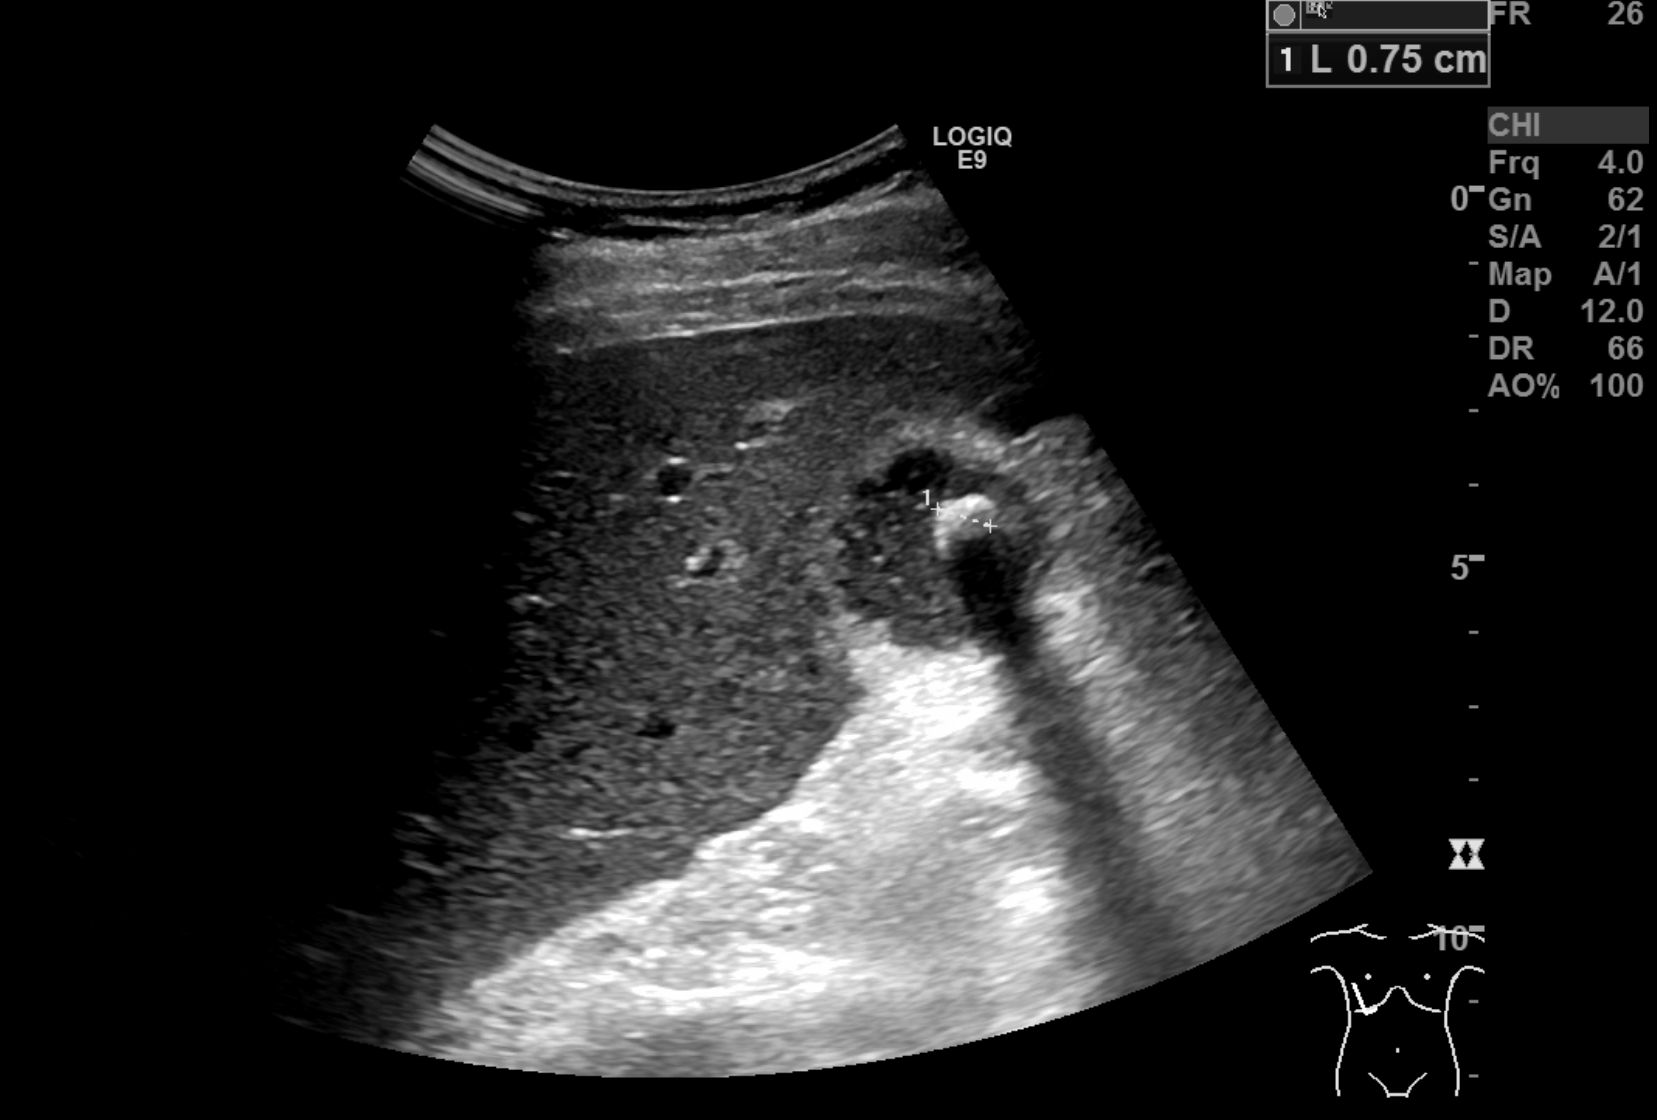

The patient was referred to ultrasound with suspicion of acute cholecystitis as a possible primary diagnosis and acute appendicitis as a secondary possibility. An ultrasound examination of the abdomen was performed using a GE Logiq E9 system with a curved array transducer with a frequency of 1-6 MHz (GE, Chalfont St. Giles). The examination revealed sludge and a stone of approximately 1 cm in the gallbladder. There was no dilatation of the intra- or extrahepatic bile ducts and the gallbladder wall was without thickening (below 3 mm). The other abdominal organs were normal. The appendix could not be seen. Due to the discrepancy between the clinical history, the imaging findings and the planned cardiac surgery the day after, a CT examination was performed to exclude appendicitis. CT showed pericholecystic fat stranding, confirming the diagnosis of cholecystitis. The appendix was located behind the cecum and appeared normal. No other pathology was reported.